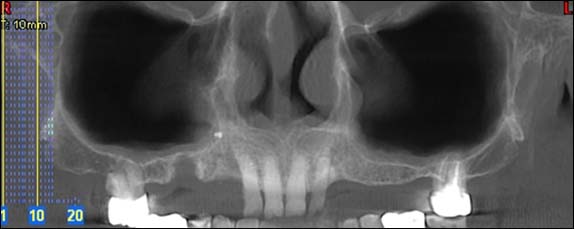

Téléradiographie de profil et de face

Ces examens sont principalement réalisés dans le cadre d’un traitement ODF ; ils ont pour but de permettre un diagnostic et un pronostic précis pour entreprendre un traitement.